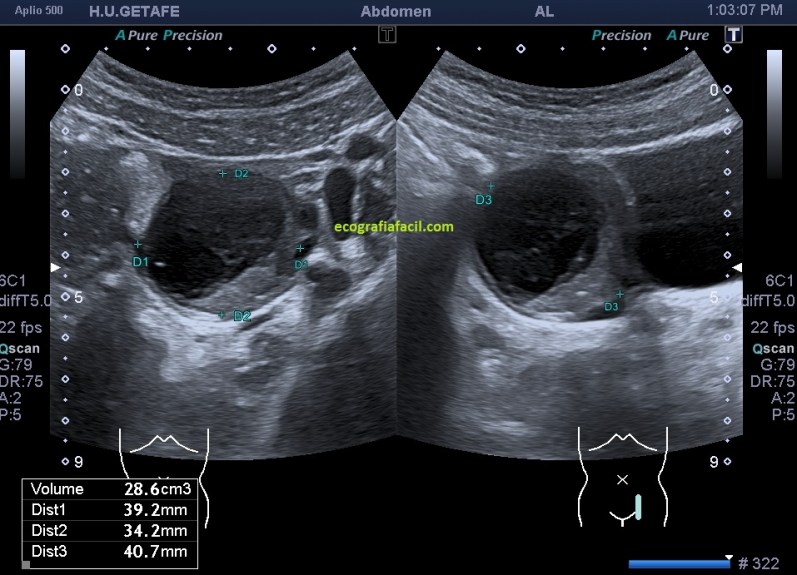

En la imagen 7 ves la lesión que te he contado antes, circunscrita y medida, se demuestra que pertenece al ovario izquierdo, con un folículo diminuto y anecoico, que puedes verlo señalado por la flecha amarilla y hueca y dentro de esta estructura, la lesión, de aspecto quístico con contenido ecogénico.

En la imagen 8, medidas y volumen del quiste, que solo él, es siete veces mayor que ovario derecho.